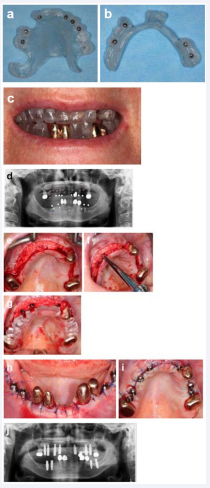

In a three hour operation in general anesthesia we removed the upper jaw residual dentition (Figure 12a), lifted the tissue by means of a full flap (Figure 12b), removed the inflammatory tissue (Figure 12b) and leveled the residual bone (Figure 12c).

Figure 12: (a) Removing the residual dentition in the upper jaw, (b) the inflammatory tissue thoroughly, (c) levelling the residual bone by around 2-4 mms, (d) lifting the sinus on the right side, (e) sequentially drilling for the implant cavities, (f) covering the sockets and sharp edges with xenogenic bone grafting material, (g) closing the wound and place impression copings, (h) place a composite reinforced wire to improve rigidity, (i) take the impression and (j) the bite. (k) The temporary abutments were incorporated in the denture, and were then (l) placed onto the implants and (m) the screw accesses are covered with Teflon. (n) The patient after three days with a slight swelling evident. (o) The X-ray checking the implant positions.

Due to the anterior extension of the right maxillary sinus an external sinuslift was performed and filled again with xenogenic bone of porcine origin (mp3, Osteobiol, Tecnoss/Adsystems, Vaterstätten, Germany) (Figure 12d). Following the sinuslift the implant cavities were drilled using a template (Figure 12e). After inserting the implants (Nobel Active, Nobel Biocare, Kloten, Switzerland) with a torque between 50 and 70 Ncm, the mesostructure was placed with 35 Ncm (Multi-units straight and angled, Nobel Biocare). Now we filled the extraction sockets using xenogenic bone of bovine origin (BioOss, Geistlich, Baden-Baden, Germany) and membranes (Osseoguard, Zimmer Biomet) (Figure 12f). After suturing the wound, we placed impression copings for open tray impressions (Figure 12g), connected them via an individually bent orthodontic wire and composite (Ceramill, Amann-Girrbach, Pforzheim) (Figure 12h) and took an impression (Permadyne, 3M Espe, Landsberg am Lech, Germany) (Figure 12i). Afterwards the bite was taken with the prefabricated denture (R-SI-Line, Metal-bite, R-dental, Hamburg, Germany) (Figure 12j). The impression and the denture including the bite were delivered to the laboratory. In approximately three hours the temporary abutments were inserted into the denture and the denture relined. Six hours after the patient entered the surgery we placed the denture with 15 Ncm and covered the screw access holes with Teflon. After three month a metal framework was placed into the denture and the denture was relined. The patient’s teeth are monitored and cleaned half yearly.